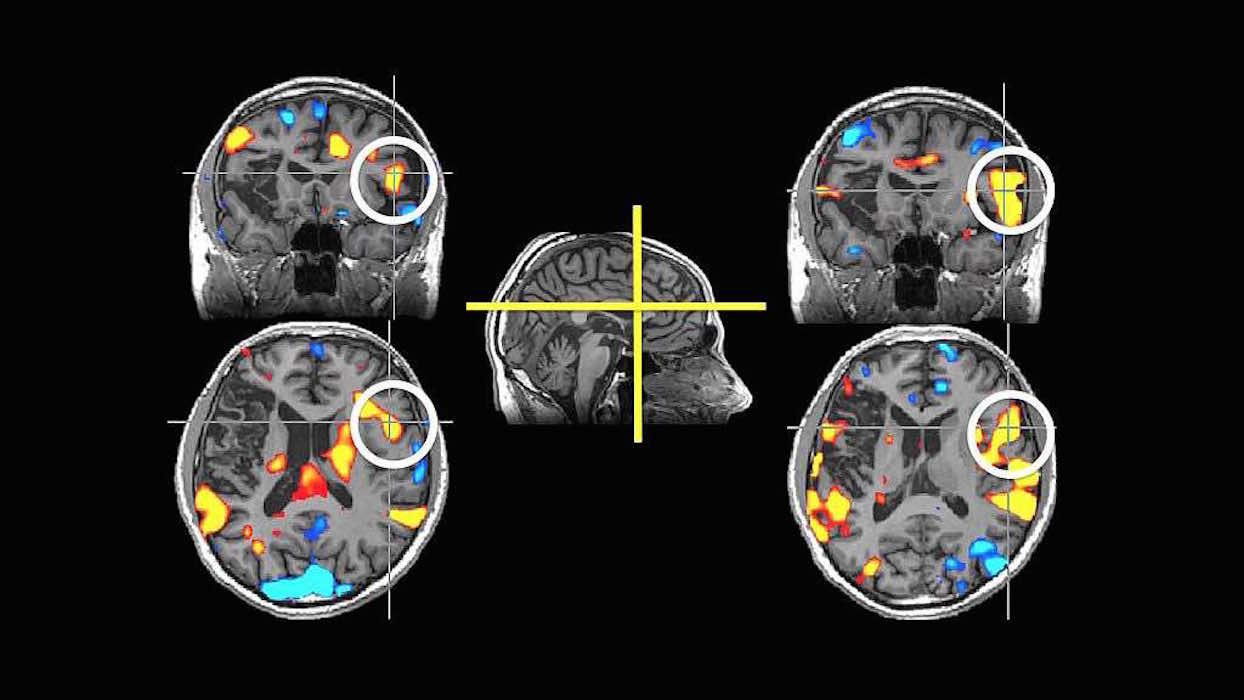

stroke1024